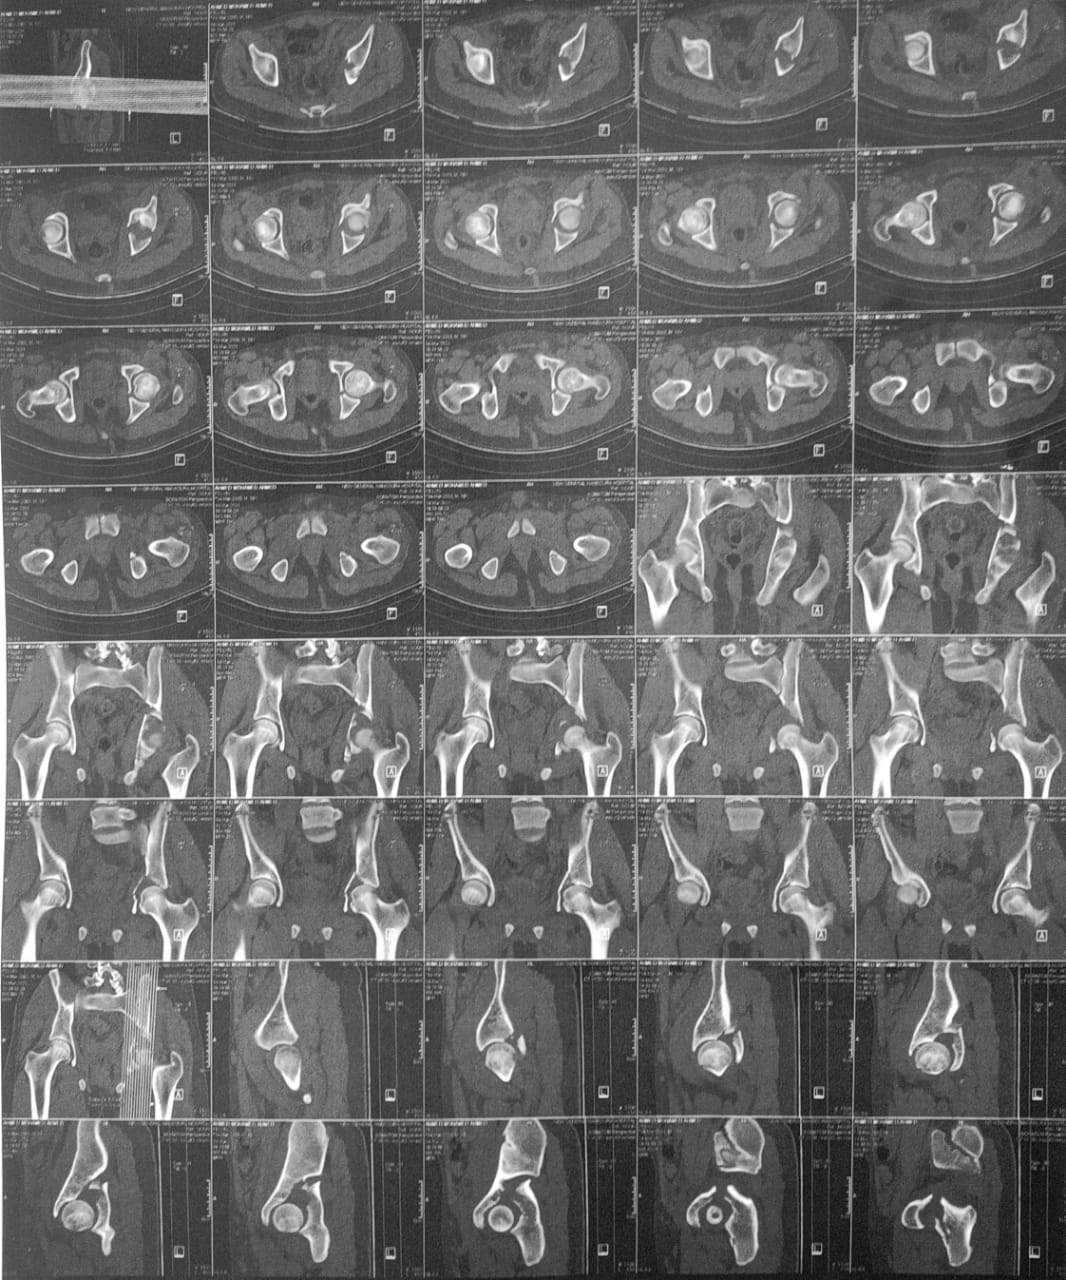

أعلن الدكتور سعد مكي وكيل وزارة الصحة بالدقهلية عن نجاح فريق طبي في إنهاء معاناة شاب يبلغ من العمر 20 عاما كان يعاني من كسر بحق مفصل الفخذ الأيسر مع خلع بالمفصل مع تأثر العصب الوركي وتمكن الفريق الطبي من إجراء جراحة عاجلة لرد الخلع وتثبيت الكسر بشرائح ومسامير معدنية وعمل استكشاف للعصب الوركي.